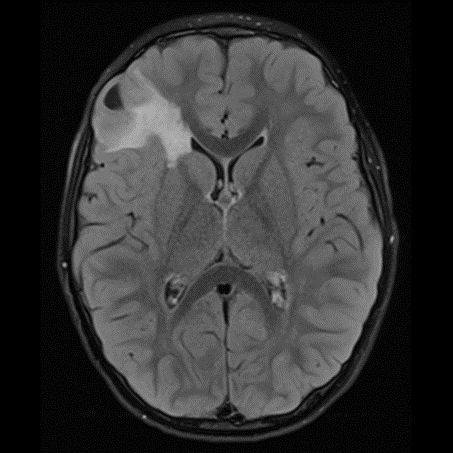

DNET:Özellikle erkek çocuk ve nöbet öyküsüyle gelen hasta kortikal yerleşim ve t1 ağırlıklı serilerde hipointens t2a ve flair serilerde ise hiperintens görülmesi bu tanıma uymaktadır. Hastaların 5’te birinde frontal lobda da tutulum olabilir. Lezyon çevresinde ödem ya da içerisinde kalsifik odak izlenmemiştir:

DNET:Özellikle erkek çocuk ve nöbet öyküsüyle gelen hasta kortikal yerleşim ve t1 ağırlıklı serilerde hipointens t2a ve flair serilerde ise hiperintens görülmesi bu tanıma uymaktadır. Hastaların 5’te birinde frontal lobda da tutulum olabilir. Lezyon çevresinde ödem ya da içerisinde kalsifik odak izlenmemiştir.